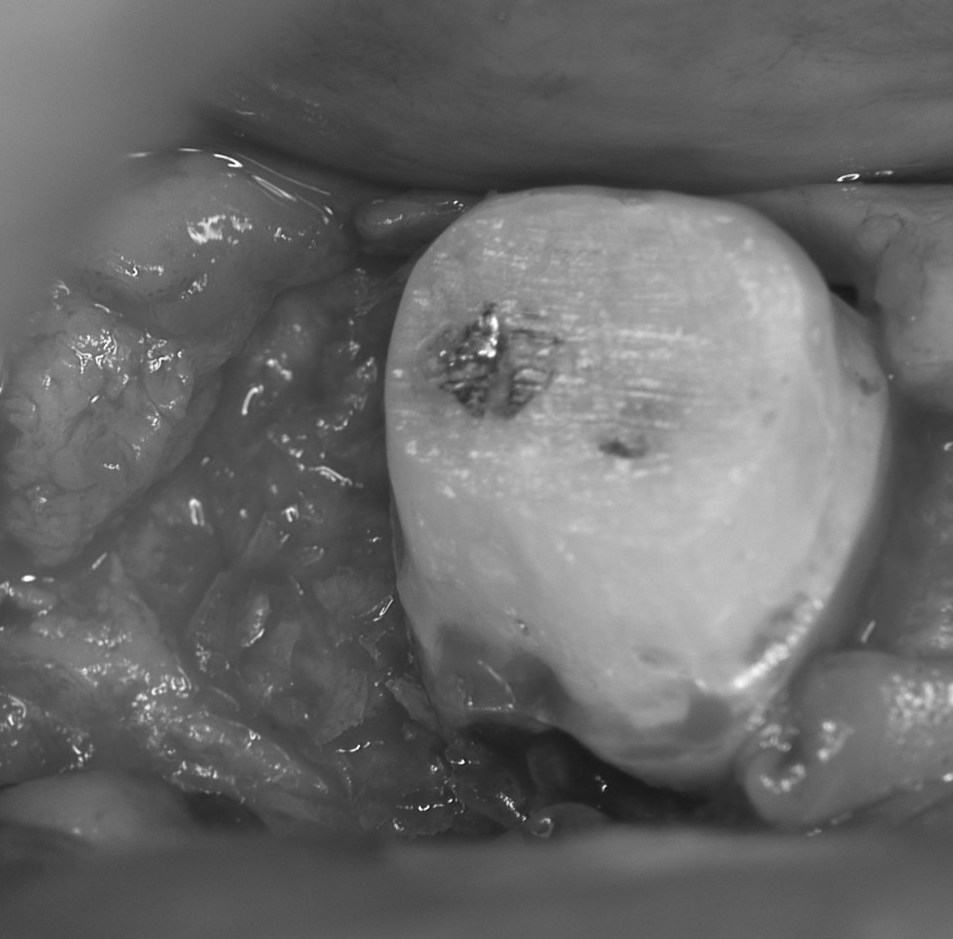

再生手術時の写真です。歯肉を切開・剥離した後に,骨が溶けて膿みが溜まっている部分を廓清し,歯石を除去しました。

骨面も根面もきれいにした後に,再生材料を骨欠損部に充填します。このケースでは自家骨移植を行いました。多くの場合,骨移植のみではなくエナメルマトリックスタンパク(エムドゲイン)やPDGFなどの成長因子を併用します。